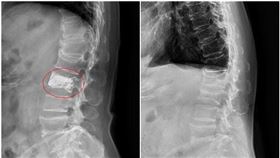

驚現「胸椎腫瘤」 醫:良性也恐癱瘓

75歲劉女士患有骨質疏鬆症,四年前因腰痛骨折至台北慈...